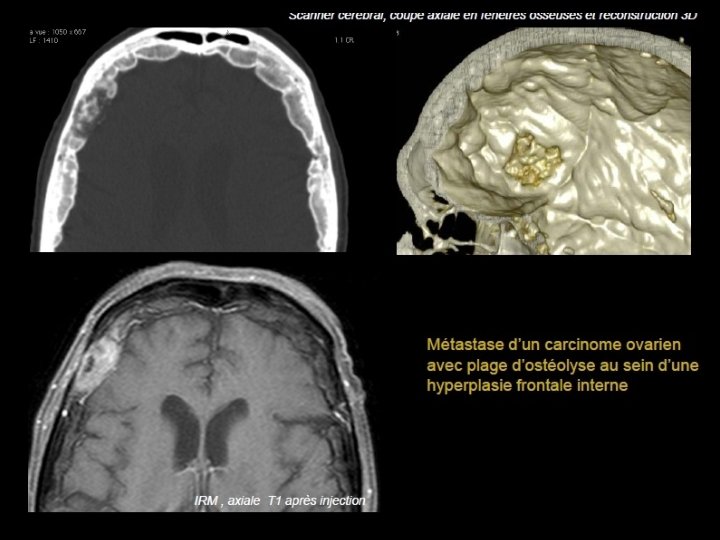

Métastases • Cause la plus fréquente des tumeurs de la voûte • À partir de la 5ème décade • PPRST+++: poumon, prostate, rein, sein, et thyroïde. • Lésions multiples : sein et poumon • Lésion unique, soufflante : rein et thyroïde • Enfant : Neuroblastome étiologies à évoquer en 1 er

• Scanner: - Plus volontiers lacunaires que condensantes. - Initialement diploïques - Destruction secondaire des tables interne et externe - Envahissement des parties molles et de l’espace épidural • IRM - T 1: Hypo ou isosignal effaçant l’hypersignal habituel du diploé, - T 2: Hypersignal - Prise de contraste.